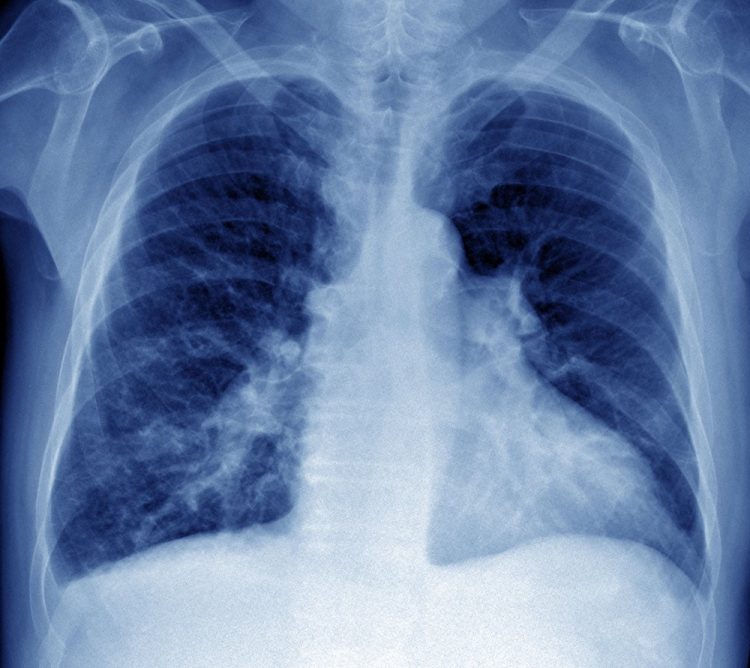

Older patients with pulmonary arterial hypertension (PAH) may have lower pulmonary artery compliance and worse right ventricular performance compared with their younger counterparts, according to a study published in The Journal of Heart and Lung Transplantation.

With an increasingly aging population of patients with PAH, there is an urgency to better understand the relationship between age, hemodynamics, and exercise capacity to determine reliable indicators of PAH-specific disease severity in elderly patients.